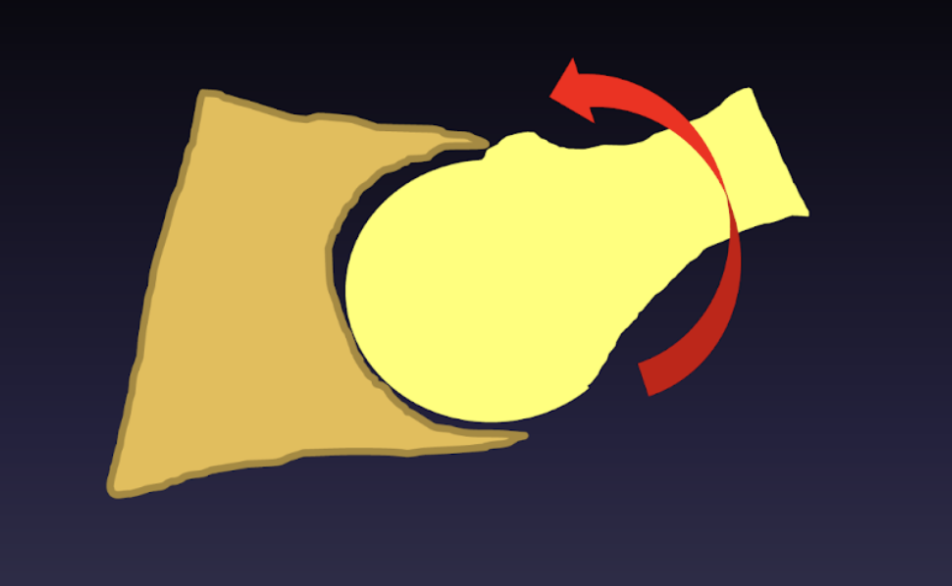

- Type à came : Caractérisé par une bosse sur le col du fémur, ce type entraîne un contact précoce des structures osseuses lors des mouvements de la hanche.

- Type à pince : Ce type est dû à une déformation de l’acétabulum, entraînant un contact osseux précoce similaire.

Le conflit fémoro-acétabulaire, également connu sous le nom de conflit antérieur de la hanche, se réfère à une interaction anormale entre la cavité de l'os du bassin et le col du fémur pendant les mouvements de hanche. Cette interaction peut causer des dommages au cartilage et au labrum, provoquant douleurs et limitations de mobilité.